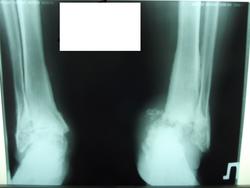

Фотки слишком контрастные, костной структуры практически не видно. А клиника-то какая? Хронические болячки, травмы в анамнезе? Слева подвывих стопы кнутри и кзади, причина - что угодно, от гнойного артрита до спинального поражения. Двусторонняя таранно-пяточная коалиция, мож и анкилоз - не могу разобрать, есть ли вообще составная щель в подтаранном суставе.

Вот именно что попросили проконсультировать снимки а не больную. Валентин Львович, если можно, пожалуйста обработайте снимки с помощью ваших програмных гаджетов. Попробовал обработать сам.Видел в амбулаторной карте консультацию травматолога Ставит "асептический некроз неяясного генеза".

Эх, дорофей, дорофей, что снимок без клиники - кусок полупрозрачного полимера. Судя потому, что некроз предполагается асептический, клиники воспаления нет. Тогда, больше всего это похоже на нейрогенную остеоартропатию. Вот что пишет на эту тему учитель наш, Самуил Аронович Рейнберг:

Прошу прощения за обширную цитату, но, в данном случае, образней Рейнберга не скажешь. Возможно, это действительно люетическое поражение, а возможно нейрогенная остеоартропатия иного (например, диабетического, или опухоли спинного мозга) генеза.

Вот именно что у больной тяжелое течение сахарного диабета. Уточняю, звонил коллеге, он подтвердил диагноз

стопа Шарко - это изменения в суставе Лисфранка, а он в зону исследования не вошел.

Мой дифф ряд: последствия инфекционного артрита, ОАП, прыжки с высоты.